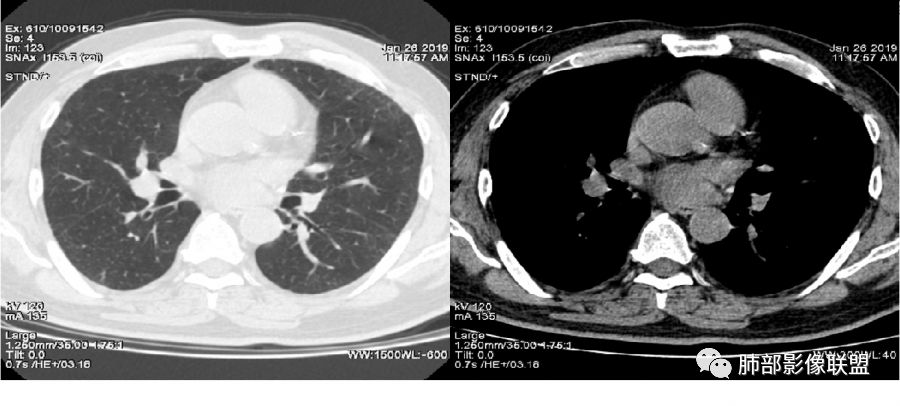

老年女性,右肺下叶沿胸膜下大片状高密度影,外周磨玻璃影,边界较清,内可见蜂窝征及支气管充气征,考虑肺炎型肺癌。

老年女性,咳嗽咳痰病史,右肺下叶大片磨玻璃实变影,胸膜下分布,支气管进入后扩张、僵直,磨玻璃影边界清楚,考虑粘液腺癌。鉴别肺炎。

右肺下叶基底段靠胸膜实变/磨玻璃混杂密度影,边界清楚,内见多发空泡(蜂窝样趋势改变?); 临床:咳嗽咳痰,无发热、胸痛; 考虑腺癌:无发热,感染性病变不首先考虑;部分层面形态类楔形,鉴别肺栓塞

老年女性,右下肺实变影,病灶里有小叶内间质增厚,周围GGo,支气管扩张,粘液性腺癌?淋巴瘤?

中年女性,咳嗽咳痰。右肺下叶片状高密度影,部分实性密度,周围见边界清晰磨玻璃影,内见小空泡,实性区部分支气管堵塞,有重力效应,考虑肺炎型肺癌,建议查痰脱落细胞。

老年人,右肺下叶斑片状阴影,病灶有膨胀性,边缘可见磨玻璃影,其边界清晰,内见僵硬的支气管,部分支气管扩张,首先考虑占位性病变,粘液性腺癌可能。鉴别感染性病变,后者边缘多有收缩性改变或者平直,内部支气管走形自然。

1.本例病灶较大片混杂密度影,胸膜下分布为主(未沿着支气管分布),该分布特点可见于大叶性肺炎、干酪性肺炎、淋巴瘤及粘液腺癌等。可惜未提供增强扫描图像。

2.病灶示中央实变区,周围GGO,可见明显小叶间隔增厚,GGO边界清楚,应当考虑到恶性病变的可能性。肺炎因炎性水肿及渗出,影像上边界常模糊不清,注意早期粘液腺癌可出现似清非清的边界。粘液腺癌因粘液成份较多,密度一般偏低,纵隔窗病灶常会消隐或范围会明显缩小,这不同于炎性实变。

3.病灶内支气管走形略显僵直,侧支少(粘液阻塞),也符合肺腺癌的枯树枝征。而大叶性肺炎的支气管是管壁光整、通畅、自然,结核的支气管常常壁增厚,甚至狭窄后扩张;